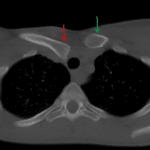

- Posterior dislocation of the right sternoclavicular joint with a tiny chip fracture along the anterior aspect of the right clavicular head

- Sternoclavicular joint dislocation

Posterior dislocation of the right sternoclavicular joint with a tiny chip fracture along the anterior aspect of the right clavicular head. Recommend chest CTA with delayed imaging through the superior mediastinum to further evaluate for traumatic vascular injury.